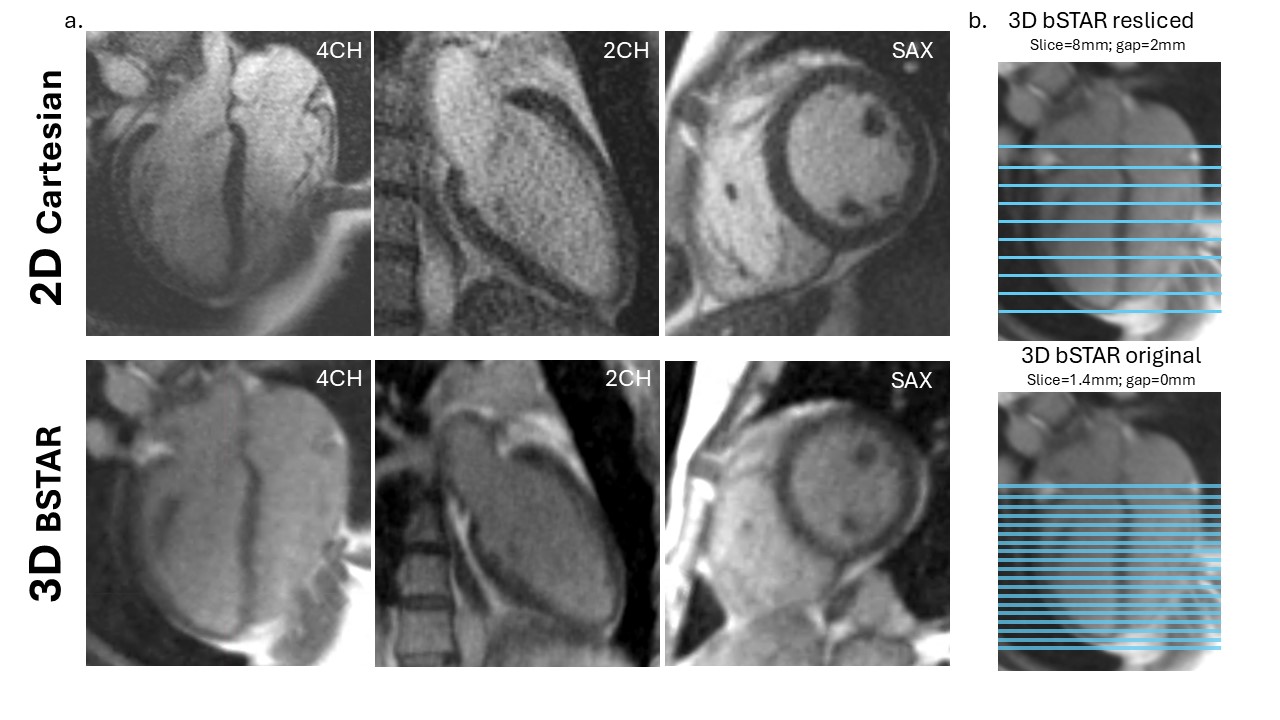

Figure 2. Bland-Altman analyses of resliced bSTAR and original bSTAR vs 2D for LVEF, LVESV, and LVEDV. The solid line corresponds to the mean bias and the dotted line corresponds to the 95% upper and lower limits of agreement (LOA). Patients (PT) represented in red. Healthy Volunteers (HV) represented in blue.jpg)